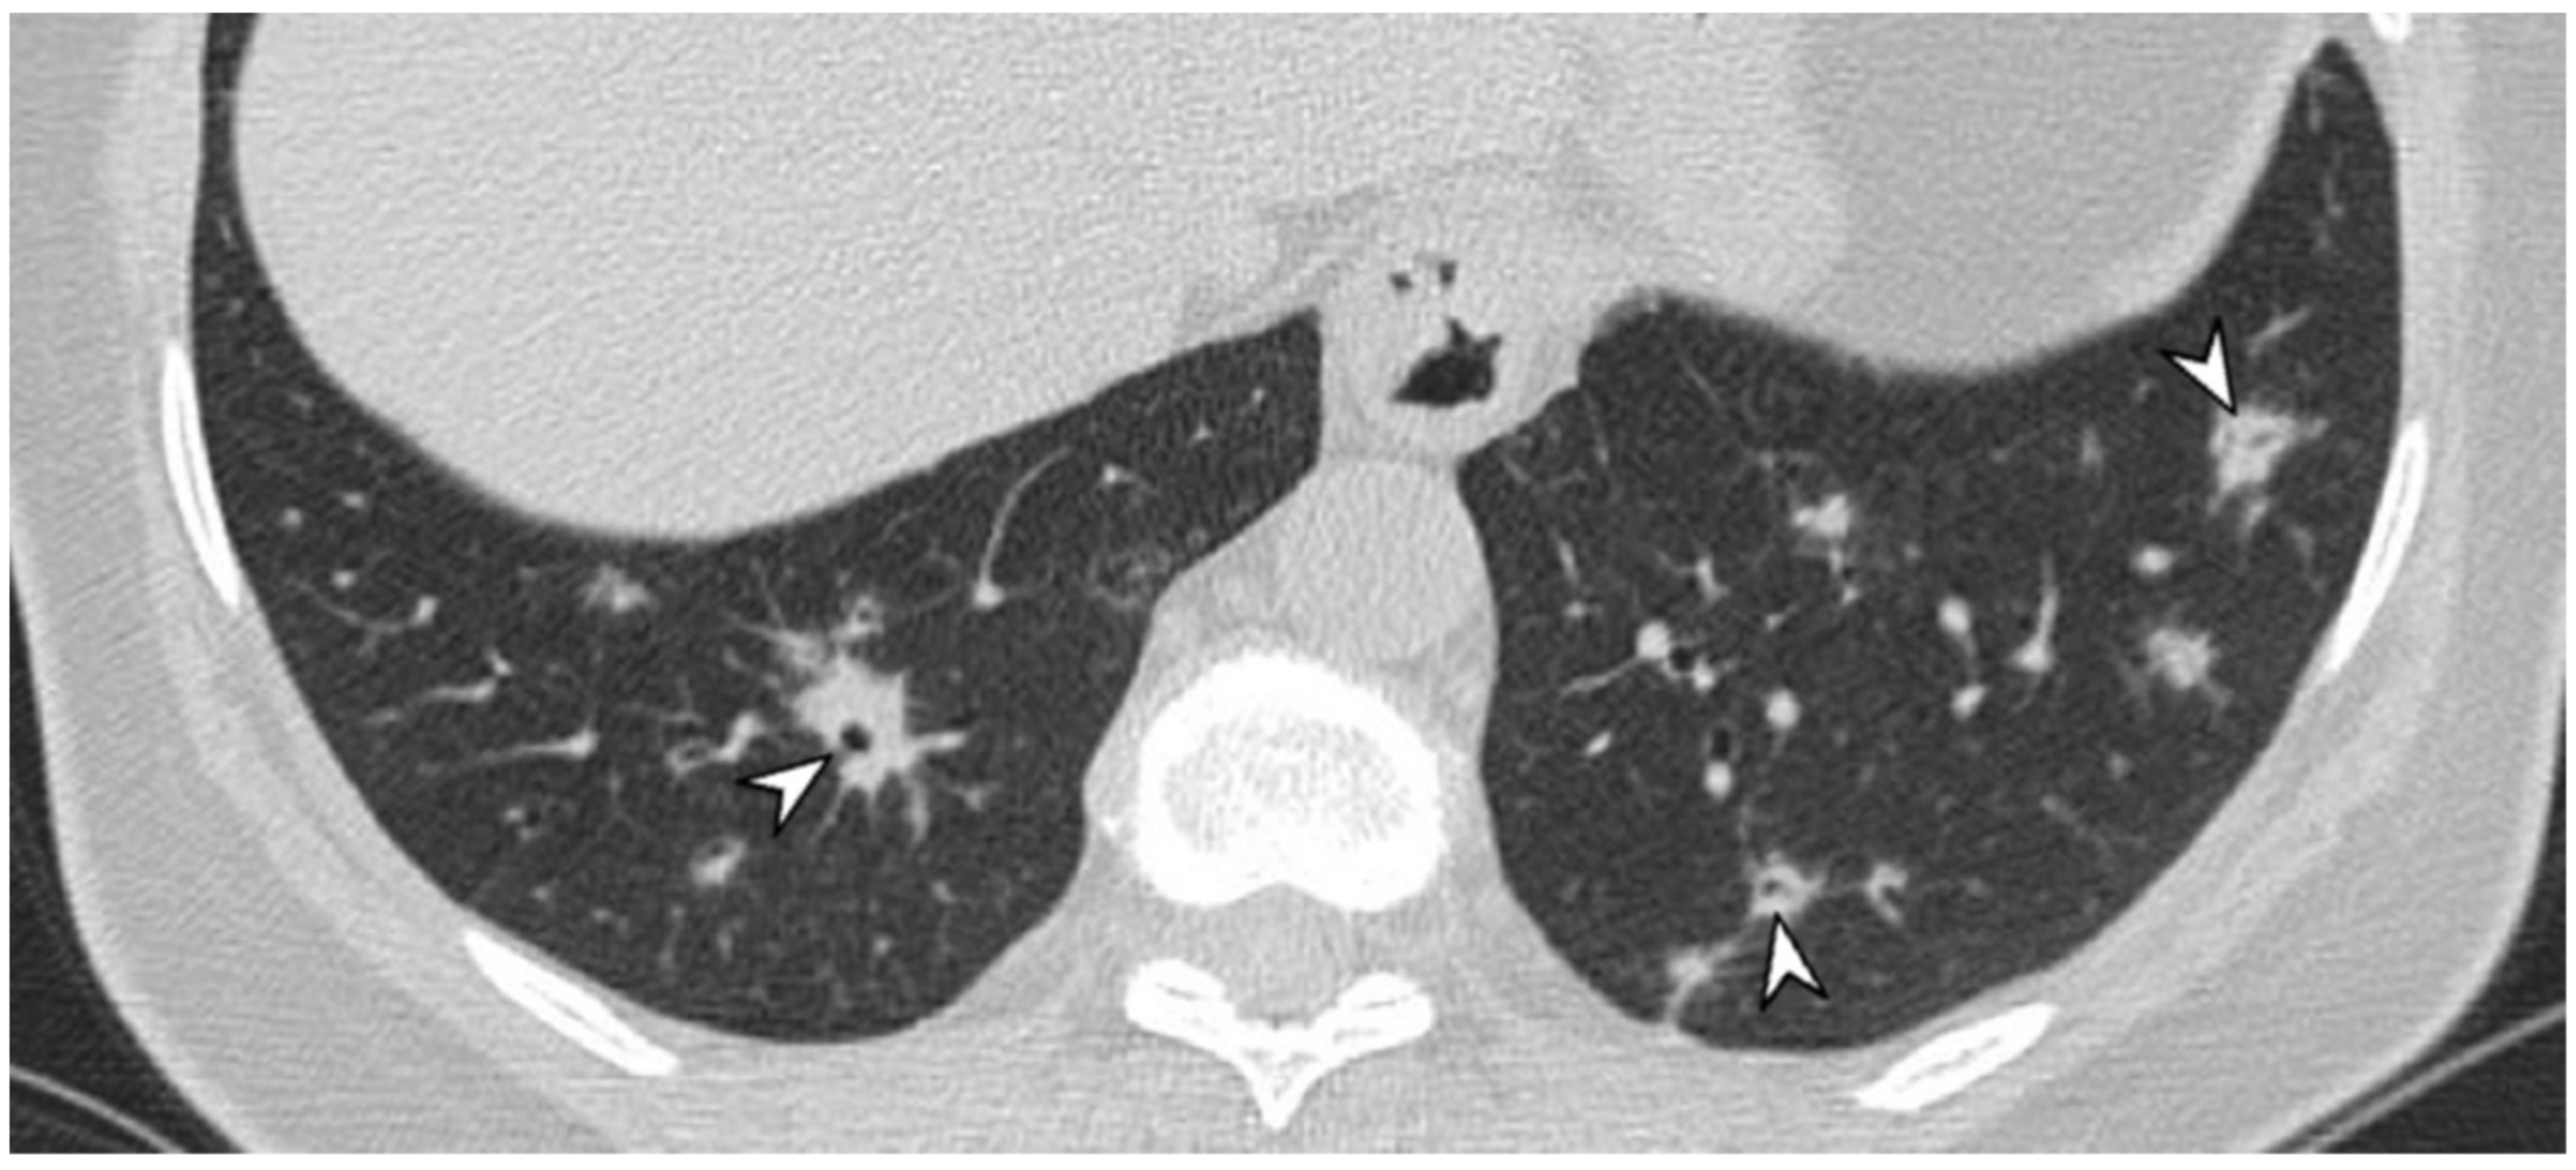

2.10. ILD in ANCA-Associated Vasculitides

2.10.2. Morphological Patterns and Imaging